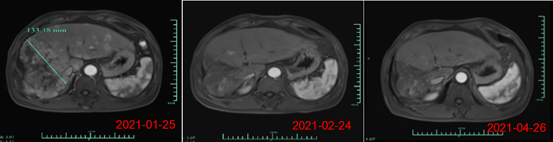

其中,受試者007的PR緩解時(shí)間超過6個(gè)月,腫瘤體積減少超過80%。截止日前該患者的緩解周期已超過8個(gè)月,仍在持續(xù)隨訪中。另一名療效顯著的受試者012是一位彌漫型、巨塊型晚期的肝癌患者,曾接受過12次以上的TACE治療,在放療及靶向治療無效后加入本研究。

回輸28天后MRI結(jié)果顯示最大腫瘤直徑從133mm減少至9mm,縮小超過93%。目前,該受試者在回輸3個(gè)月后評(píng)估,MRI掃描結(jié)果顯示此腫瘤幾乎消失。相應(yīng)地,回輸28天后其AFP(甲胎蛋白,診斷原發(fā)性肝癌特異性的腫瘤標(biāo)志物)水平從>80000降至1148.9ng/ml,回輸3個(gè)月后降至746.7ng/ml(其正常值是在0-40ng/ml以內(nèi)),展示了Ori-CAR-001在晚期肝癌治療的顯著有效性。